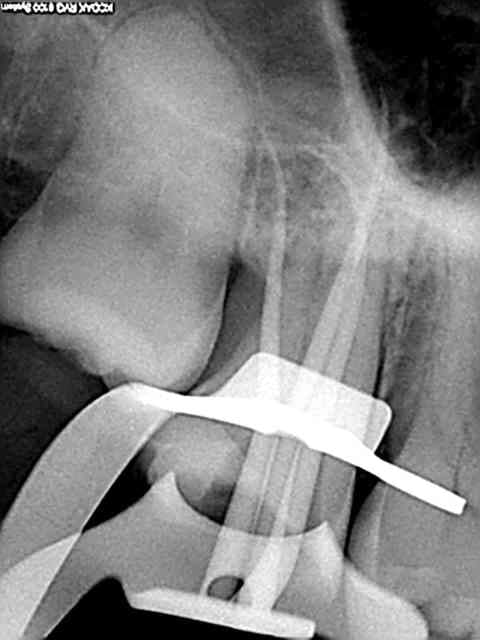

Faudrait que je la retrouve mais y'a une vidéo avec une radio qui m'a fait mal dans mon ego...

Sinon, pour répondre à la question, j'utilise un seul cône calibré Protaper, je descend avec le MacSpadden jusqu'à 5mm de l'apex sur CA bleu plein pot et ça tasse en 5 secondes (pas plus longtemps sinon ça chauffe, pas plus bas sinon ça fuse). Les astuces: un coup d'air pour dégager l'excès de ciment à l'entrée du canal avant introduction de l'instrument (le ciment fait tampon à la chaleur et gêne la fusion du cône), si ça ne suffit pas --> instrument de plus gros diamètre (il existe des sets pas chers avec des diamètres jusque 80, ça dépanne parfois sur un gros canal palatin ou après une dépose de tenon).